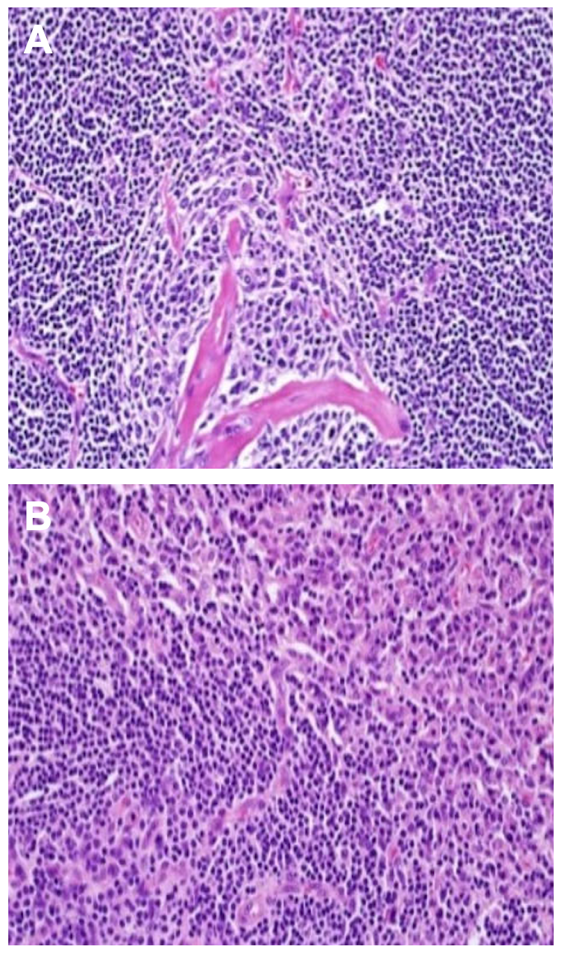

根据淋巴结病理检查,可以将Castleman病区分为三种不同亚型:透明血管型、浆细胞型和混合型(图1)。其中透明血管型是UCD最常见的亚型(75%),其病理特征比较明显,表现为淋巴滤泡中生发中心萎缩,小淋巴细胞围绕生发中心排列形成“洋葱皮外观”。而浆细胞型是 MCD的最常见亚型(75%),透明血管和浆细胞共存的混合亚型在HHV8相关MCD中最为常见,iMCD中也较为常见3。浆细胞型和混合型的特征不明显,极易与其他疾病混淆,很难诊断(图2)。

图1: Castleman病常见组织病理学改变。A:透明血管型;B:浆细胞型。